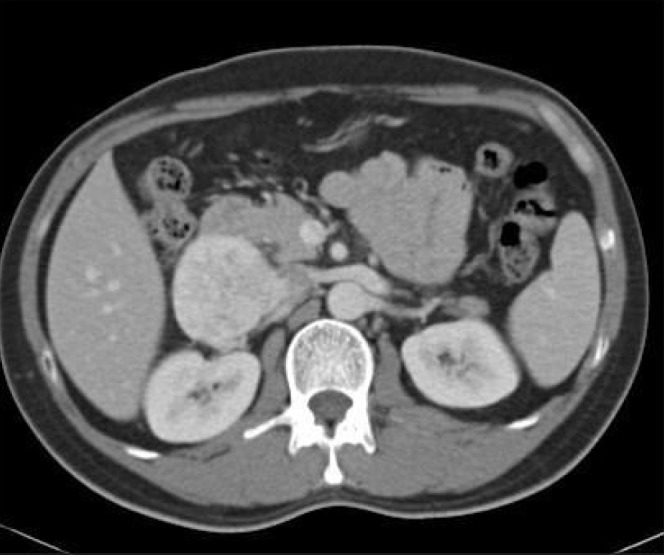

A 43-year-old Indonesian man, a hepatitis B carrier, was referred to our institution for an incidental finding of a right abdominal mass on routine ultrasonography of the hepatobiliary system as part of the screening protocol for hepatitis B carriers. He was completely asymptomatic. Computed tomography (CT) of the abdomen and pelvis demonstrated a heterogeneously enhancing right anterior retroperitoneal mass. This was inseparable from the wall of the IVC for a length of 4cm as demonstrated on CT (Fig 1). This mass was abutting against the posterior aspect of the second part of the duodenum and the inferior aspect of segment 6 of the liver but not invading into the liver. The differential diagnoses were that of a leiomyosarcoma with an extravascular component or that of a neuroendocrine tumour such as a paraganglioma. There was no evidence of pulmonary or hepatic metastases.

Figure 1.

Axial computed tomography of the abdomen of tumour invading inferior vena cava